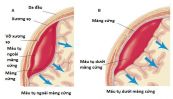

Máu tụ dưới màng cứng hình thành giữa màng cứng và màng nhện. Máu tụ ngoài màng cứng là khối máu tụ hình thành ở khoang ảo giữa màng cứng và xương sọ. Để hiểu rõ hơn về hội chứng này, mời các bạn cùng tham khảo bài viết sau đây!

Não có thể bị tổn thương do hộp sọ bị nứt hoặc đâm xuyên, ví dụ như trong trường hợp tai nạn xe cộ, rơi ngã hoặc trúng đạn, một diễn tiến bệnh tật. Để biết rõ hơn về hội chứng này, mời các bạn cùng eLip tìm hiểu trong bài viết dưới đây!

Chấn thương sọ não hở bao gồm tất cả các chấn thương sọ não gây rách màng cứng, khai thông não bộ với bên ngoài, loại này gây nguy cơ nhiễm khuẩn não cao. Để biết thêm về hội chứng nguy hiểm này, mời các bạn tham khảo bài viết dưới đây!